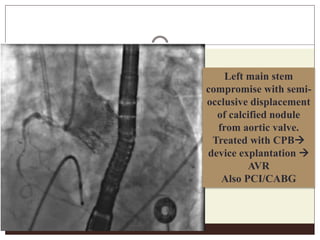

Left main stem

compromise with semi-

occlusive displacement

of calcified nodule

from aortic valve.

Treated with CPB

device explantation 

AVR

Also PCI/CABG